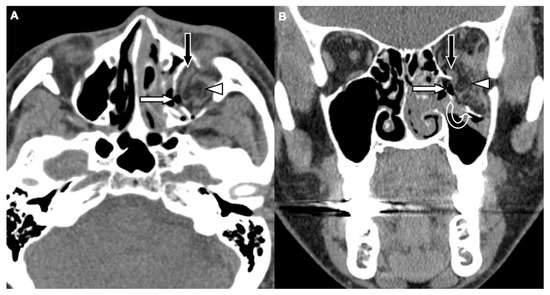

Figure 1. CT images of a 29-year-old male with assault-related head trauma and a concomitant left orbital floor fracture (OFF). An axial head CT image (A) and the corresponding coronal facial CT image (B) show gas bubbles (black arrow) entrapped between the discontinuous floor fragments (white arrows). Left type 2 maxillary hemosinus (MHS) (arrowhead) and a left zygomatic fracture are also noted in (A).

Figure 2. CT images of a 62-year-old female with motorcycle crash-related head trauma and a concomitant left OFF. An axial head CT image (A) and the corresponding coronal facial CT image (B) show inferior extraconal emphysema (straight white arrow) beneath the inferior rectus muscle (black arrow), orbital fat herniation into the maxillary sinus (arrowhead), and the depressed fragments of fractured orbital floor (open curved arrow).

Two board-licensed radiologists (L.D.J. and Y.Y.C.) who were blinded to the patients’ clinical information reviewed only the head CT images by means of consensus. The radiologists were permitted to manipulate the window and level of the images. The CT variables related to the cranium included intracranial hemorrhage (ICH; epidural hemorrhage, subdural hemorrhage, subarachnoid hemorrhage, and intracerebral hemorrhage), and skull fractures. The CT variables related to OFFs included orbital floor discontinuity (Figure 1), gas bubbles entrapped between the floor fragments (Figure 1), inferior extraconal emphysema (Figure 2), orbital fat herniation into the maxillary sinus (Figure 2), and ipsilateral maxillary hemosinus (MHS, Figure 3). MHS was defined as high-attenuation opacity at the dependent portion of the maxillary sinus measuring ≥ 45 Hounsfield units (HU) as the lower limit of attenuation for clotted blood [15]. Since MHS is a relevant indicator used to detect OFFs on CT scans [5,16], we further classified MHS into the following three CT subtypes: (1) Type 1, high-attenuation opacity mixed with mottled gas (Figure 3A); (2) Type 2, air–fluid level (Figure 3B); and (3) Type 3, full opacification of the sinus (Figure 3C).

The sensitivity, specificity, positive predictive value, and negative predictive value of MHS and its three subtypes were evaluated in detail (Figure 4). While MHS exhibited a very high negative predictive value (99.7%) for excluding OFFs, type 1 MHS had the highest positive predictive value (69.5%) for detecting OFFs compared to total MHS and the other two subtypes.